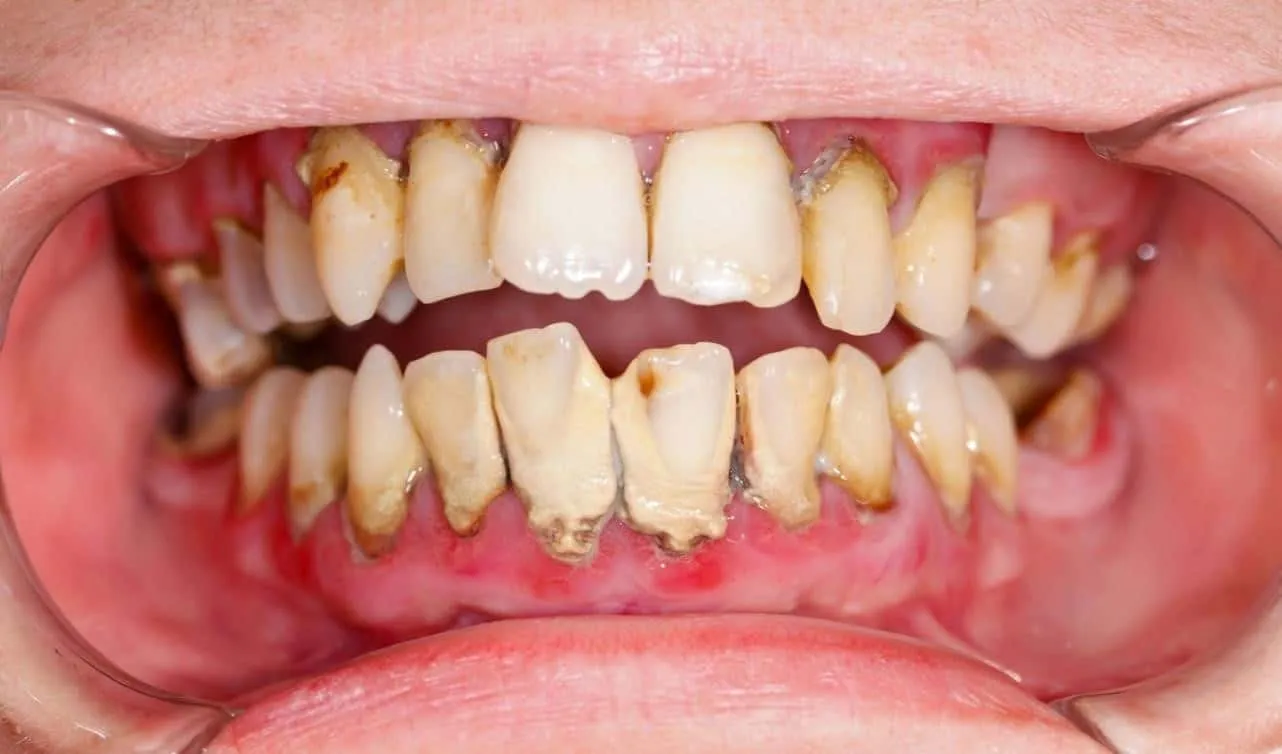

Tuy nhiên trên thực tế, mất răng gây ra hiện tượng tiêu xương hàm khiến nướu teo lại, các răng còn lại bị xô lệch. Những răng bị đổ nghiêng sẽ yếu dần, lung lay và rụng đi.

Toàn bộ hệ thống răng miệng bị sai lệch khớp cắn sẽ gây khó khăn trong việc trồng răng giả, phục hình răng sau này. Đa số mọi người đều chưa có nhận định đúng để trồng răng ngay khi nhổ hoặc đề cao việc điều trị, bảo tồn răng thật. Nhiều năm về trước, khi bị viêm nha chu, hư răng mọi người thường nghĩ đến việc nhổ hết răng để đeo răng giả tháo lắp chứ ít nghĩ đến việc điều trị giữ lại răng thật.

Trong trường hợp bệnh nhân dưới đây bị mất răng toàn hàm, trong thời gian gian và còn chịu áp lực của hàm tháo lắp nên xương hàm tiêu đi rất nhiều, nướu teo lại đáng kể.